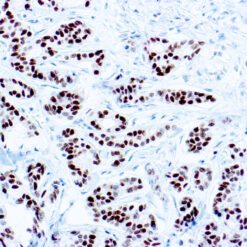

Calponin-1

Multiple isoelectric variants of calponin have been identified but only two molecular weight isoforms exist (34kDa and 29kDa). Expression of the 29kDa form, I-calponin, is primarily restricted to muscle of the urogenital tract, whereas the higher molecular weight variant has been demonstrated in vascular and visceral smooth muscle. Calponin is a calmodulin, F-actin and tropomyosin binding protein, which is thought to be involved in the regulation of smooth muscle contraction. Calponin expression is restricted to smooth muscle cells and has been shown to be a marker of the differentiated (contractile) phenotype of developing smooth muscle.

| Positive Control Tissue | Uterus |